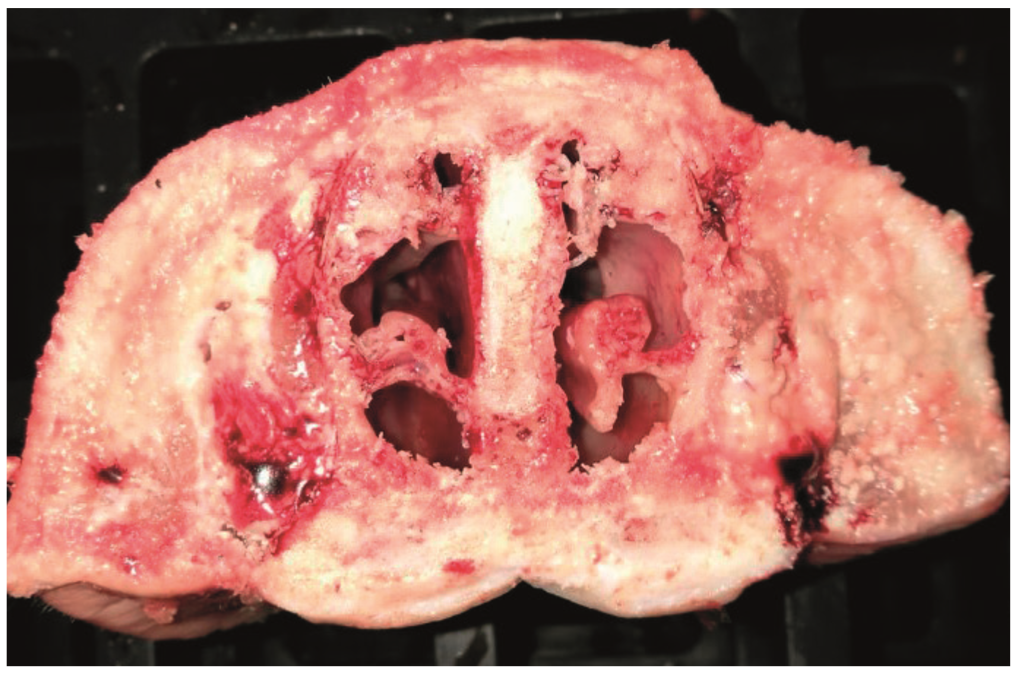

Figure 2.

Turbinate and lung lesions in a nursery pig affected by Bordetella bronchiseptica.© Histology and Anatomical Pathology, Faculty of Veterinary Medicine, University of Murcia.

Pulmonary infection with Bordetella bronchiseptica results in suppurative bronchopneumonia (Figure 2). It can act as the primary etiologic agent in young pigs and in older pigs it generally contributes to the severity of the Porcine Respiratory Disease Complex (PRDC) through interaction with other bacteria and viruses in mixed infections. The necrosis and tissue damage associated with Bordetella bronchiseptica pneumonia is induced by the action of DNT, without which pneumonia does not develop. The most prevalent clinical sign of Bordetella bronchiseptica pneumonia is coughing and it can be difficult to discern the cause without further diagnostics.